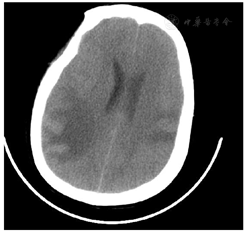

入院第18天,患者突发意识改变,呈深昏迷状态,双侧瞳孔散大固定,直径6.0 mm,对光消失,立即行头颅CT示双侧大脑半球多发低密度影,较前明显,部分为新发(图2),立即行"双侧去骨瓣颞肌下减压术+右侧Ommaya囊植入术+右顶叶脑脓肿穿刺引流术",术中见脑压高,脑搏动消失,抽出脓液及炎性破碎脑组织约25 ml。入院第19天脓液涂片报告见阿米巴滋养体(图3),脑脊液NGS回报检出棘阿米巴、卡伯德森棘阿米巴(图4),继续甲硝唑抗感染治疗。入院第24天送检脑组织病理回报:脑组织大量炎性细胞浸润,脓肿形成,脓肿内见大量阿米巴包囊及滋养体(图5)。